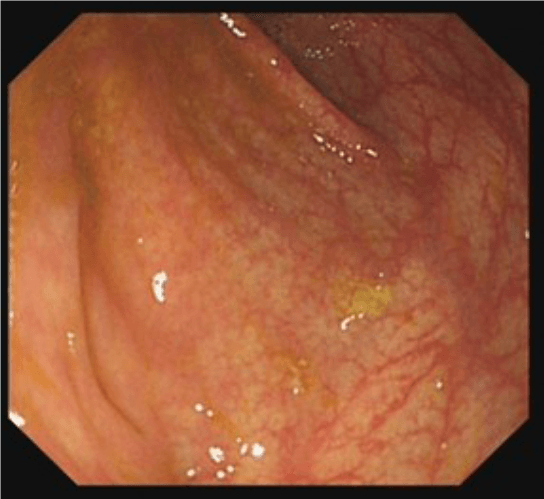

Colonoscopy involves passing a flexible tube (see image alongside) through the anus into the rectum and steering it around the colon. Some images of typical appearances are shown at the bottom of this page (hover over the images for a description).